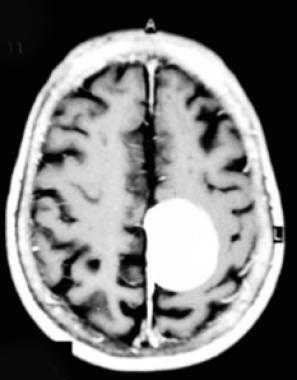

Менингиома лобной доли: КТ-картина. После введения контрастного вещества виден характерный вид «колеса со спицами» в структуре слабо контрастируемой опухоли. Несмотря на то, что данный паттерн чаще наблюдается при ангиографии, он также отмечается на томографических изображениях.

МРТ того же пациента, выполненная после предыдущей КТ: аксиальное Т1-взвешенное изображение после введения гадолиния и аксиальное Т2-взвешенное изображение. Видна крупная менингиома лобной области, расположенная срединно, со специфическим паттерном «колеса со спицами».